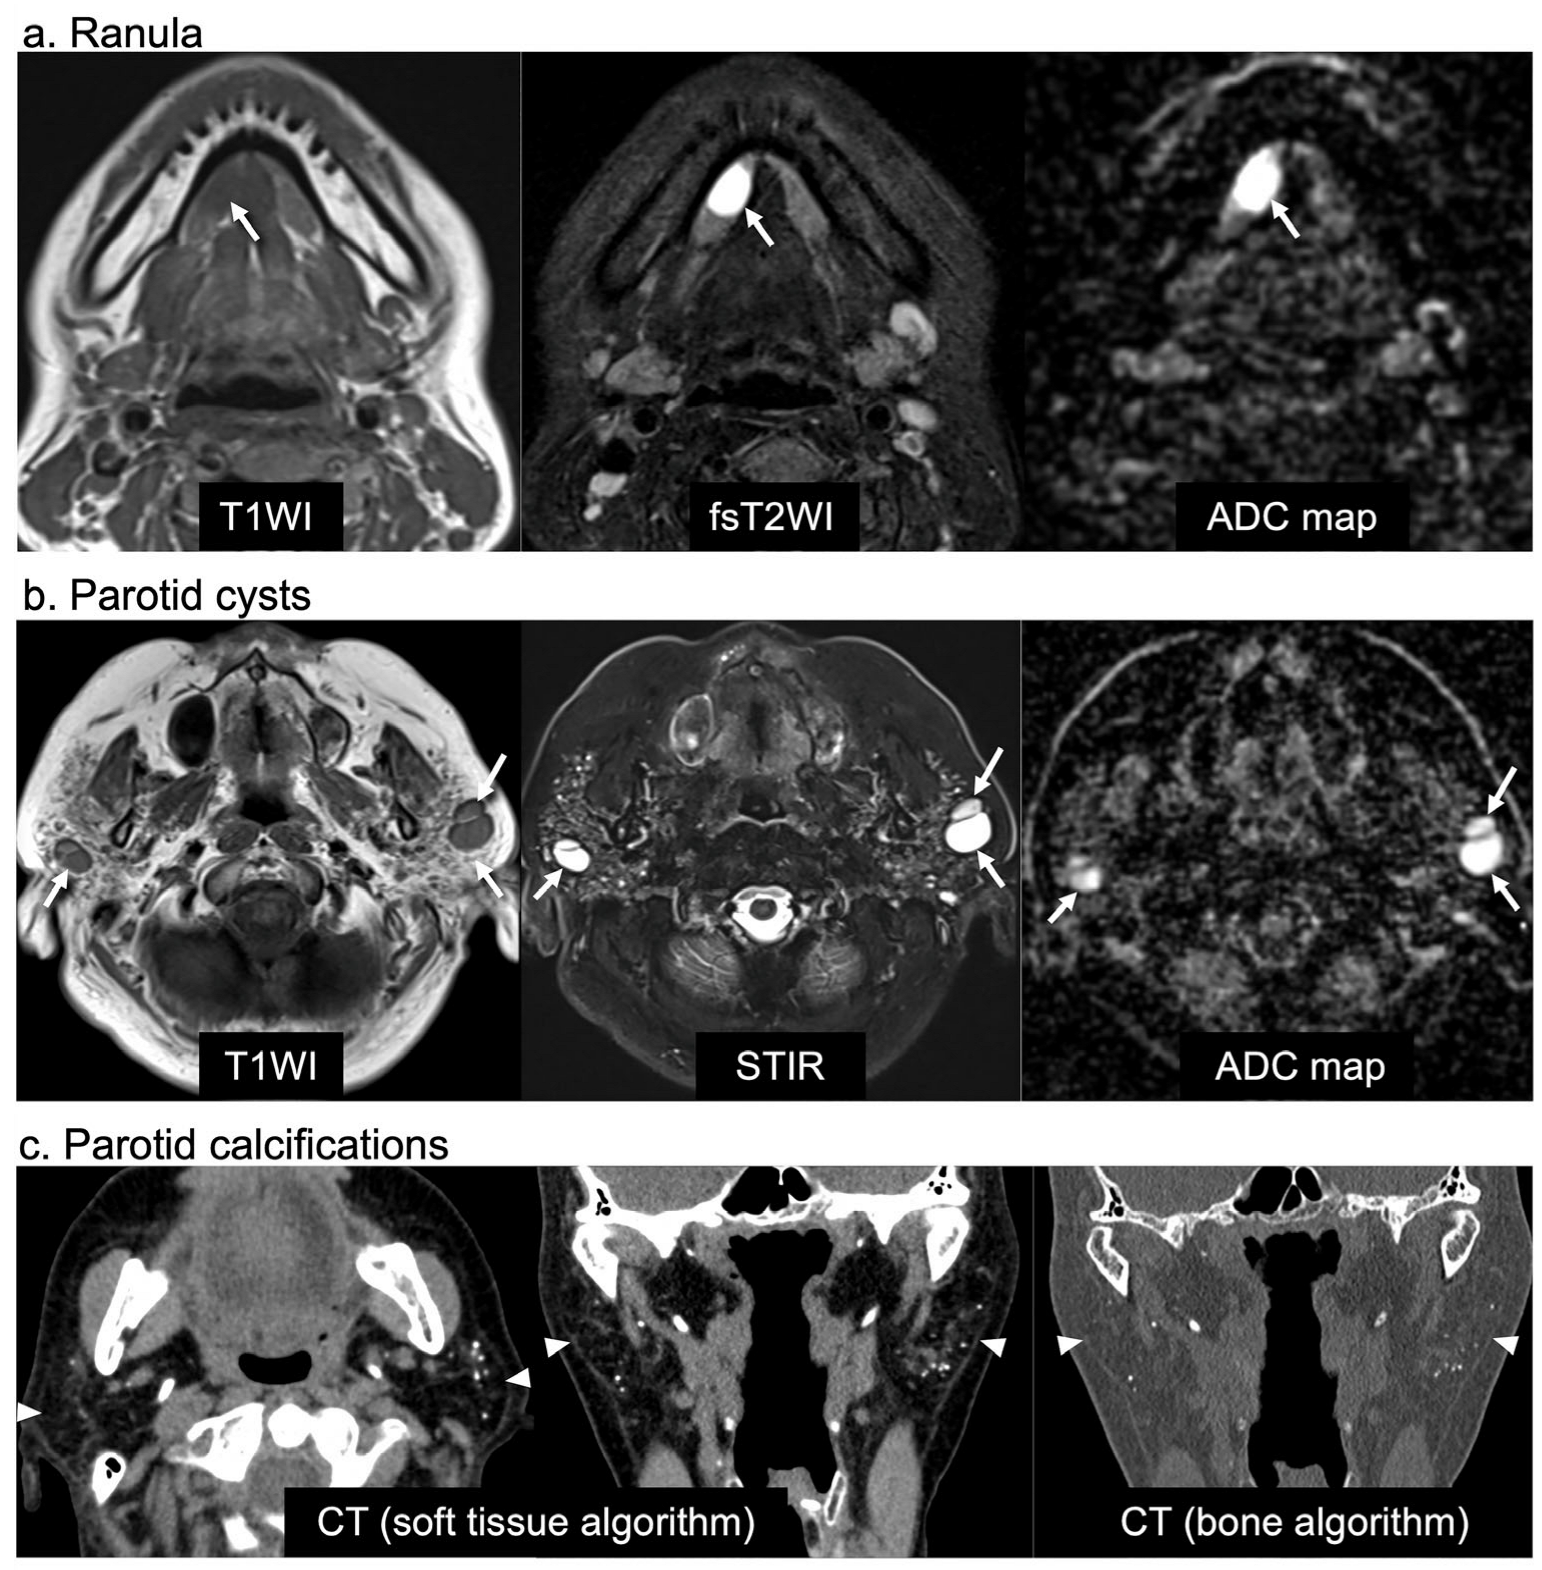

| MRI criteria (meeting a–c) | ||||

| (a) Well-defined cystic areas within or connected to sublingual glands | ||||

| (b) Marked and homogeneous hyperintense areas on fsT2WI or STIR | ||||

| (c) High ADC areas (≥2.0 × 10−3 mm2/s) [31,32] | ||||

| MRI criteria (meeting a–d) | ||||

| (a) Well-defined cystic areas with no solid portion in PGs | ||||

| (b) Maximum diameter ≥ 10 mm | ||||

| (c) Marked and homogeneous hyperintense areas on fsT2WI or STIR | ||||

| (d) High ADC areas (≥2.0 × 10−3 mm2/s) [31] | ||||

| CT criteria | ||||

| Calcifications (>100 H.U.) in PGs on non-contrast enhanced CT | ||||